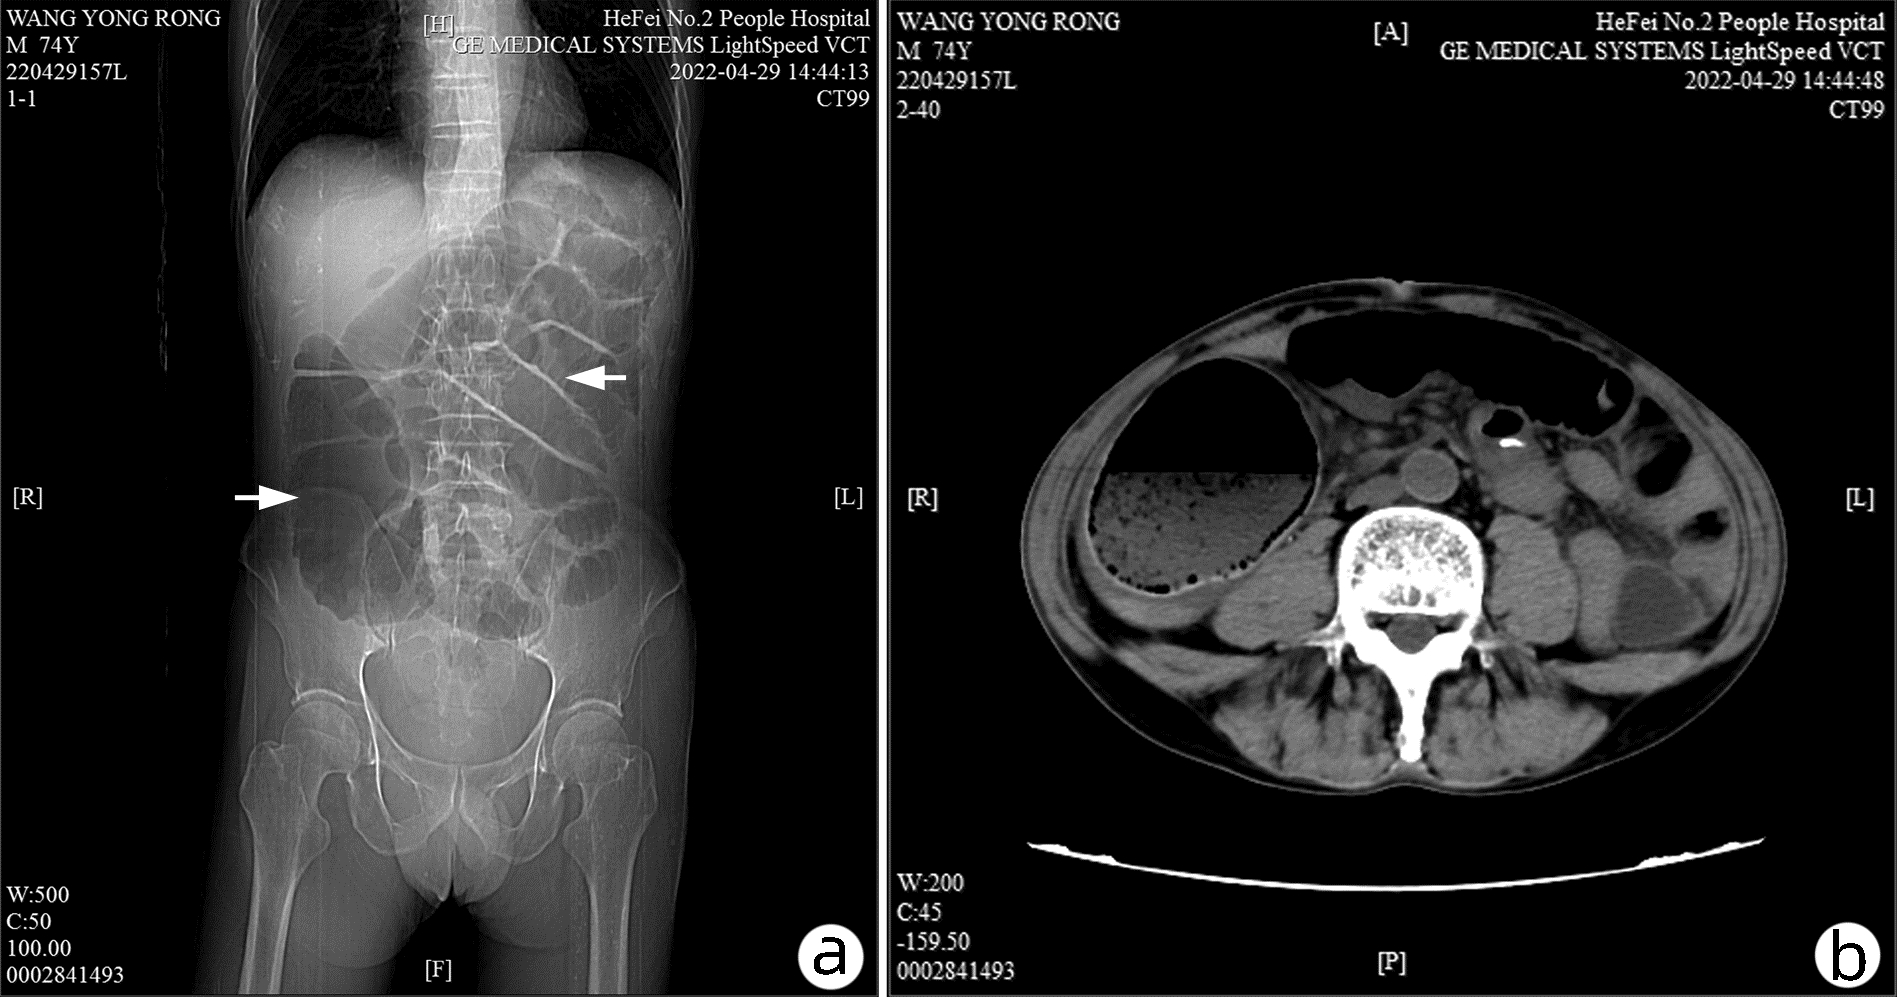

Cholecystoduodenal fistula with gallstone ileus accompanied by colon cancer: A case report

Wenbo LI, Liang LI, You JIANG, Jun ZHANG, Jun LU

2023, 39(4): 904-908. DOI: 10.3969/j.issn.1001-5256.2023.04.024

Abstract(925) HTML (226) PDF (2744KB)(60)

Abstract: